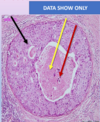

4

Section in?

Causative organism?

Type of inflammation?

Red and blue arrows?

Diagnosis?

A

End of ileum and caecum

Shigella bacilli

Acute non-suppurative pseudo-membranous

Red: caecum Blue: Ileum

Bacillary dysentery